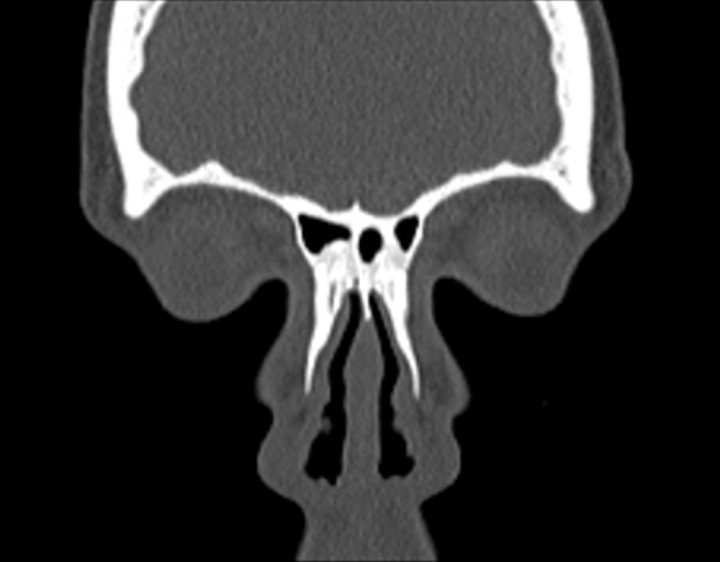

Click any image for labels.